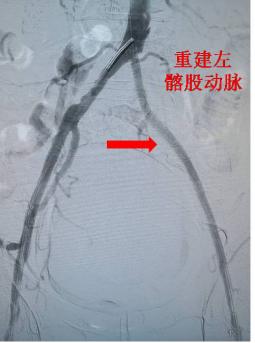

杨林教授主导完成手术,术中证实患者髂动脉-股动脉的长段闭塞,通过血管穿刺微创手术成功开通闭塞血管,置入小口径人工血管支架,重建血管血流,患者术后在护理团队帮助下,快速康复,并于今日出院。患者高兴的说是血管外科团队给了自己第二次生命,并向杨林教授团队送上锦旗致谢!

杨林教授团队成功实施此类新型手术,保障了患者在微创治疗的同时创伤更少,新型的小口径人工血管支架相比原来的微创手术,创伤更小需要血管直径更小,因此更符合人体血管形态,对血管损伤最小;该新型支架内衬低分子肝素涂层,可以保障术后血管的中长期通畅,手术效果最优。近年来,杨林教授致力于下肢动脉闭塞、血栓闭塞性脉管炎、糖尿病足等下肢血管病变的微创及手术治疗,完成多例次西北首例的下肢血管微创手术。